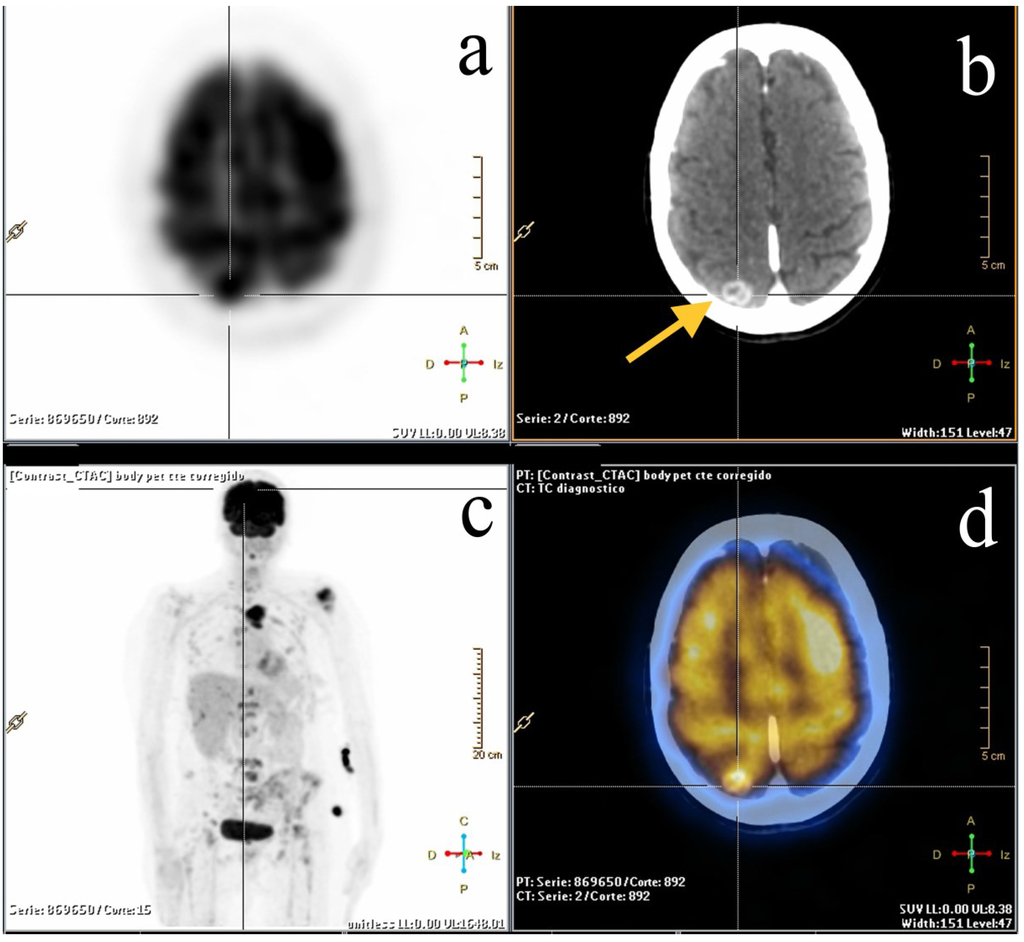

2.2. Staging and Re-Staging

2.3. Treatment Response Evaluation